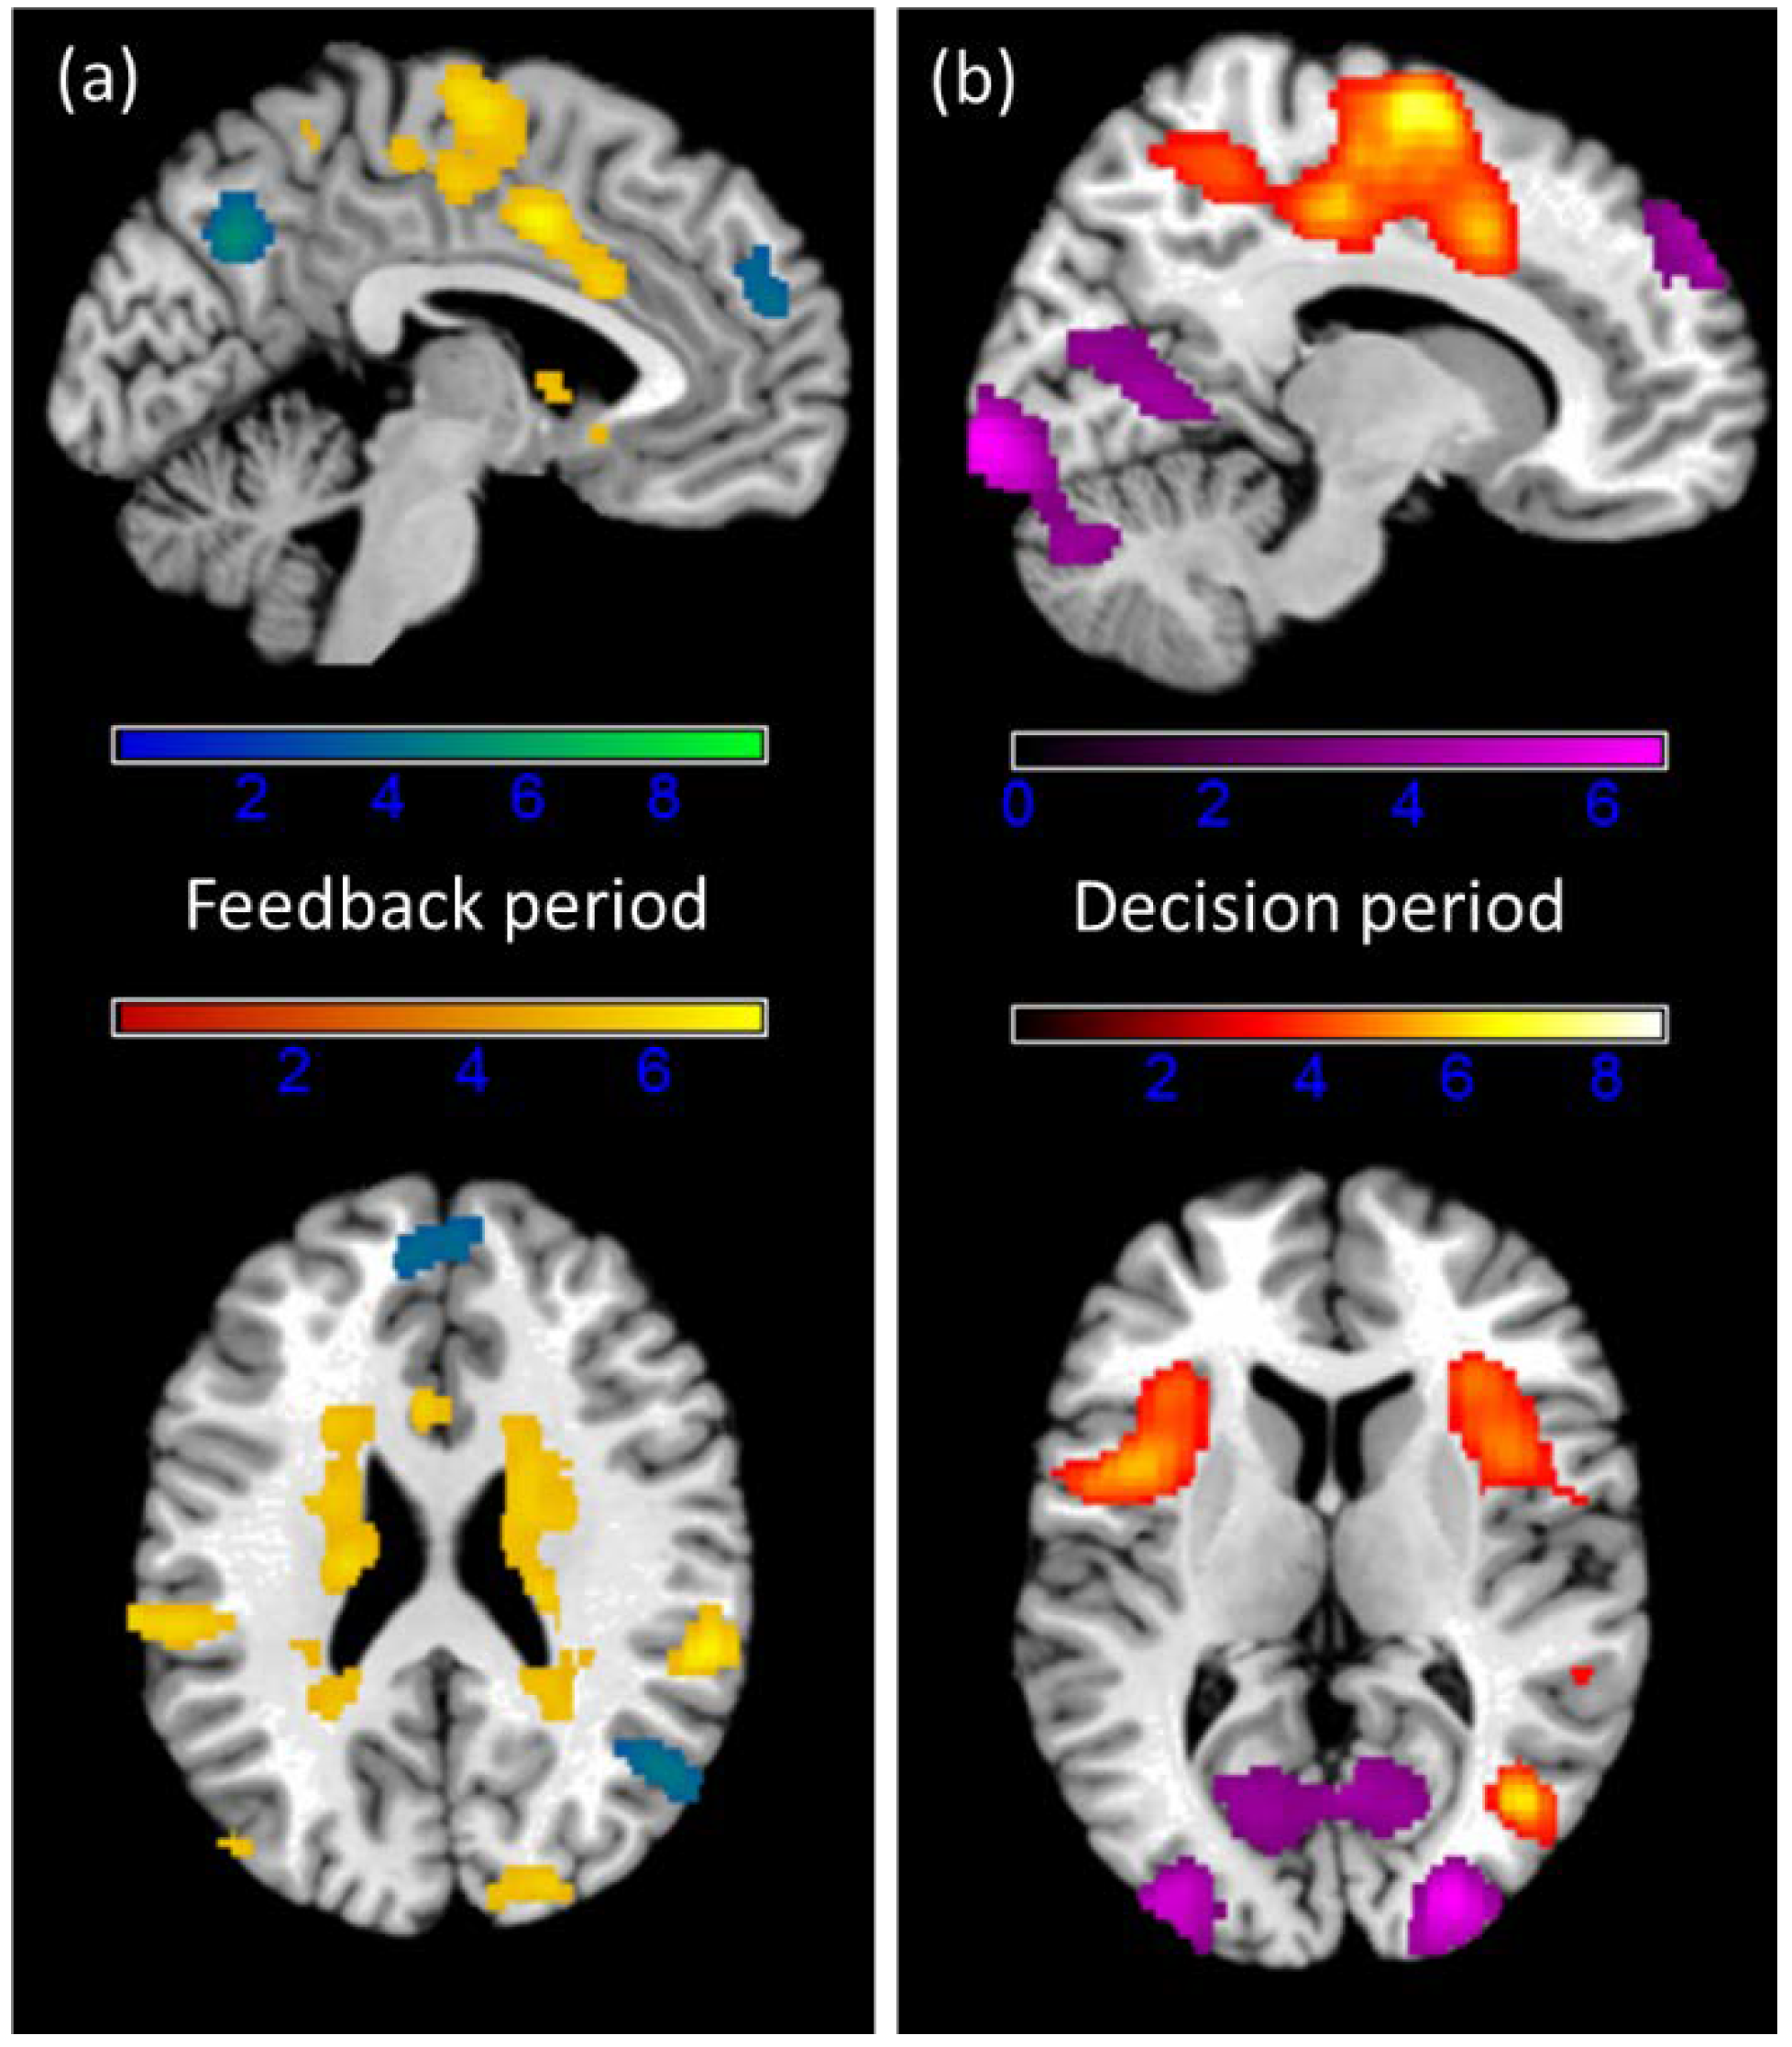

3.4. fMRI Results

4.2. Hormonal Modulation of Brain Signals